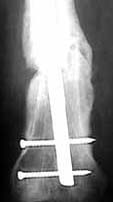

Seeking advice on further management of 26 years old male with femoral nonunion. He sustained femoral shaft fracture in a RTA 3 years ago and was treated with Open K nailing and Thomas Splint 3 years ago. See attached Xray. He was mobilised 3 months later. For about a year he was walking well then he developed pain in his knee. Xray attached show that the K nail had migrated into the Knee joint. K nail was exchanged with dynamic locking nail ( two distal screws - no proximal screw ) by closed technique - no bone grafting done. Patient was symptom free for about 18 months now has come with pain in the knee on weightbearing. Xrays attached show femoral nonunion with loosening of the distal screws (Area of lucency around the screws ). He is short fat male ( 5 feet 4 inches - 90 Kgs ), nonsmoker with no clinical or hematological signs of infection.

AP now

Lat now

This is a hypertrophic non-union, which means that it needs more stability than the interlocking nail is able to provide. I would suggest a 95 degree AO blade plate and bone grafting.